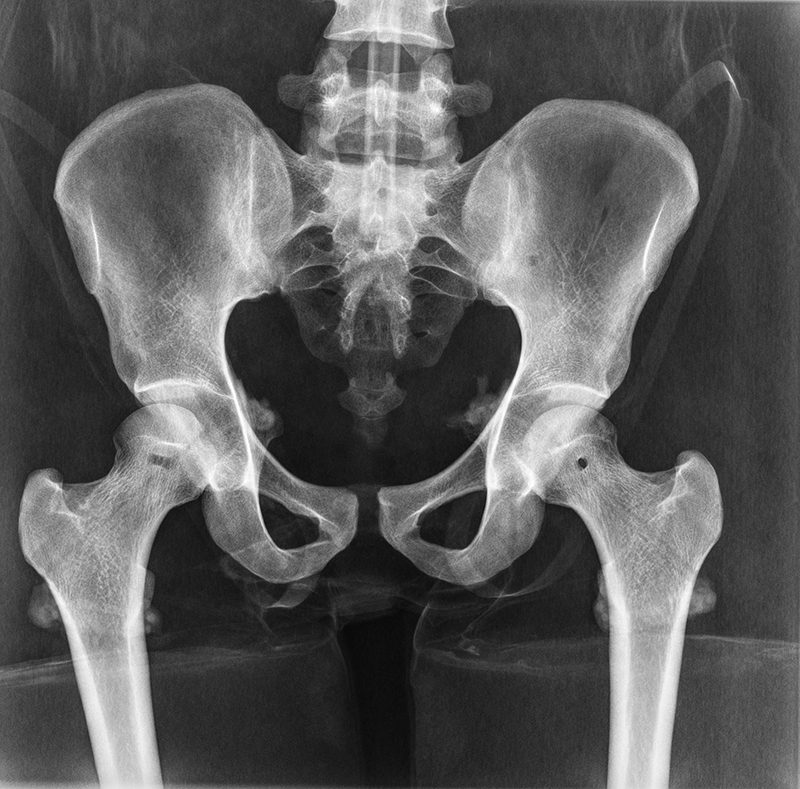

Dieses weltweit einmalige Phantom bietet erstklassige Übungsmöglichkeiten für die Lagerungs- und Einstelltechnik in der Projektions-Radiographie und gehört eigentlich zur Grundausstattung jeder Röntgen-Ausbildungsstätte. Das Phantom enthält ein natürliches menschliches Skelett sowie die Umrisse von Kehlkopf, Lunge, Herz und Nieren (Organe erscheinen als Schatten auf den Röntgenbildern), dadurch können mit dem Phantom echte Röntgenaufnahmen wie beim Patienten gemacht werden. Durch die Verwendung des echten Skeletts können Leitstrukturen im Knochen erkannt werden, was bei Kunststoffskeletten nicht möglich ist. Bei der Montage des Phantoms wird besonderer Wert auf die Darstellung der Gelenkspalte gelegt. Die Gelenke sind voll beweglich montiert, und ermöglichen die Lagerung in den normalen Röntgenpositionen (z.B. Froschposition, Pro- und Supination des Unterarms). Die Arme können nach oben bewegt werden, so dass das Modell auch für alle knöchernen Untersuchungen im CT verwendet werden kann. Bei jedem Phantom handelt es sich um ein handgefertigtes Unikat, welches sich in Größe und Ausführung unterscheiden kann. Je nach Modell können pathologische Befunde vorhanden sein, die äußere Erscheinung kann sich je nach Größe des Modells unterscheiden. Die neue Ausführung dieses Modells wurde in Zusammenarbeit mit einer namhaften deutschen Schule für Med. Techn. Radiologieassistenten komplett überarbeitet und erfüllt alle Anforderungen für die Ausbildung. Der Verkauf dieses Phantoms erfolgt nur gegen Nachweis der medizinischen Verwendung. Natürliche Größe.